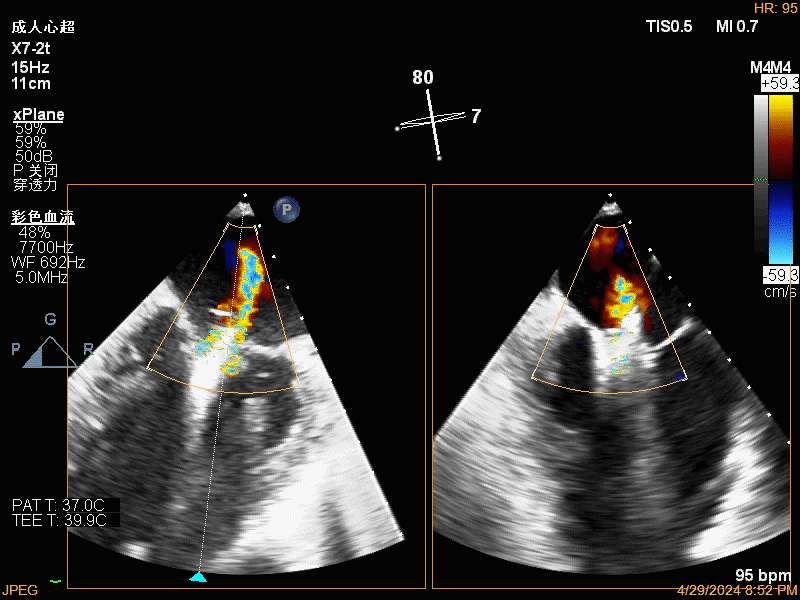

团队在反流最严重的2区精准植入1枚二尖瓣夹,即刻反流下降至微量,血压即刻上升20mmHg,跨瓣压差不升反降,由3mmHg降至2mmHg,改善效果明显,手术仅耗时一个半小时。 这是时隔四年继2020年指导开展区域内首例TAVR(经导管主动脉瓣置换)手术之后,陈茂教授再次带领华西团队,指导开展内自同城区域首例TEER术。陈茂教授对四院心内科心超图像的采集、房间隔穿刺的技巧、手术流程细节的把握、团队的默契配合、术前术后的管理表示称赞,鼓励四院心内科再接再厉造福区域患者。 患者为71岁老年女性,反复出现心累、气促已经超过10年,10多年来心衰的症状逐渐加重,间隔时间越来越短,且近1个月来已经3次因心衰住院,本次住院前已经无法耐受缓慢步行、如厕等日常生活,BNP超过了3000ng/ml。心电图为房颤,心超示左心室明显增大(65mm),重度二尖瓣反流(4+,CarpentierI+IIIb型),射血分数仅为31%。前叶长度:2.27cm且瓣尖增厚,后叶长度:1.14cm且局部钙化,瓣口面积:4.08cm2,反流宽度:1.7cm。患者及家属均拒绝外科开胸手术。 难点: 1.食道超声下该患者房间隔较厚较韧,且粗测高度仅为4.0cm,对穿刺的位置和技巧有较高要求; 2.左心扩大,反流宽度约17mm,放一个夹子可能不能有效解决反流,如放两个夹子需side by side 平行放置,但放置两个夹子有术后狭窄的风险; 3.前后叶对合似有间隙,若选用长宽夹子,会增加瓣叶张力,有瓣叶撕裂的风险,若选用短宽夹子,其捕获瓣叶的难度将增加; 4.患者心功能极差,手术需稳、准、快,不能耐受任何并发症风险。 影像资料 房间隔穿刺